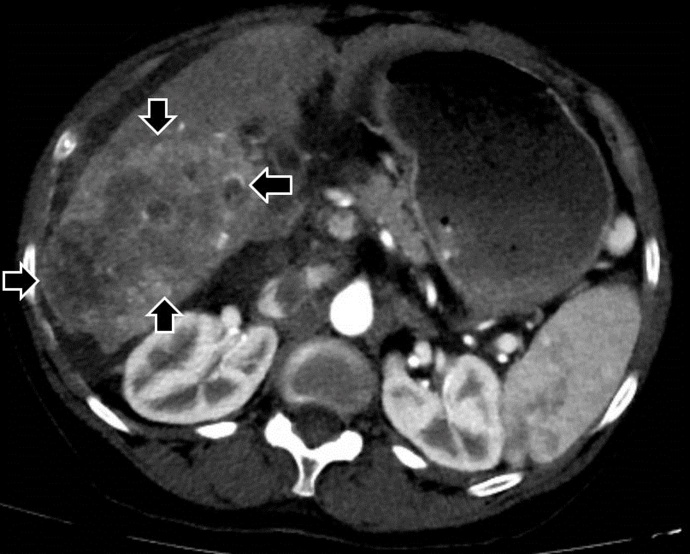

肝细胞癌是美国最常见的肝脏恶性肿瘤之一。预后不良与副肿瘤综合征有关,如高钙血症、高胆固醇血症或低血糖。高钙血症是肝细胞癌的一种副肿瘤综合征,很少有报道。我们报告了一例偶然诊断的肝细胞癌伴恶性体液高钙血症的死亡病例。该患者在最初诊断的40天内表现出暴发性病程,并出现意外的致命结果。我们的病例表明,当肝细胞癌与恶性肿瘤的体液高钙血症相关时,早期明确治疗、密切监测和积极治疗具有重要意义。

Hepatocellular carcinoma is one of the most common liver malignancies in the United States. Poor prognosis is associated with paraneoplastic syndromes such as hypercalcemia, hypercholesterolemia, or hypoglycemia. Hypercalcemia as a paraneoplastic syndrome of hepatocellular carcinoma has been rarely reported. We report a mortality case of incidentally diagnosed hepatocellular carcinoma associated with humoral hypercalcemia of malignancy. The patient demonstrated a fulminant disease course with an unexpected fatal outcome within 40 days of initial diagnosis. Our case can suggest importance of early definitive treatment of hepatocellular carcinoma, extremely close monitoring, and aggressive medical treatment when it is associated with humoral hypercalcemia of malignancy.